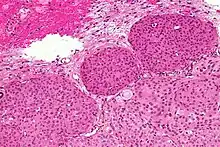

- A woven architectural pattern

- Psammoma bodies (spheroid calcifications)

- Syncytial cells (having indistinct cell membranes) with eosinophilic (pink) cytoplasms

- Round uniform nuclei

- Whorls (concentric cell arrangements)[15]

Meningiomas arise from arachnoidal cap cells,[16] most of which are near the vicinity of the venous sinuses, and this is the site of greatest prevalence for meningioma formation. Some subtypes may arise from the pial cap cells that migrate during the development together with blood vessels into the brain parenchyma.[17] They most frequently are attached to the dura over the superior parasagittal surface of frontal and parietal lobes, along the sphenoid ridge, in the olfactory grooves, the sylvian region, superior cerebellum along the falx cerebri, cerebellopontine angle, and the spinal cord. The tumor is usually gray, well-circumscribed, and takes on the form of the space it occupies. They usually are dome-shaped, with the base lying on the dura.

Histologically, meningioma cells are relatively uniform, with a tendency to encircle one another, forming whorls and psammoma bodies (laminated calcific concretions).[18] As such, they also have a tendency to calcify and are highly vascularized.